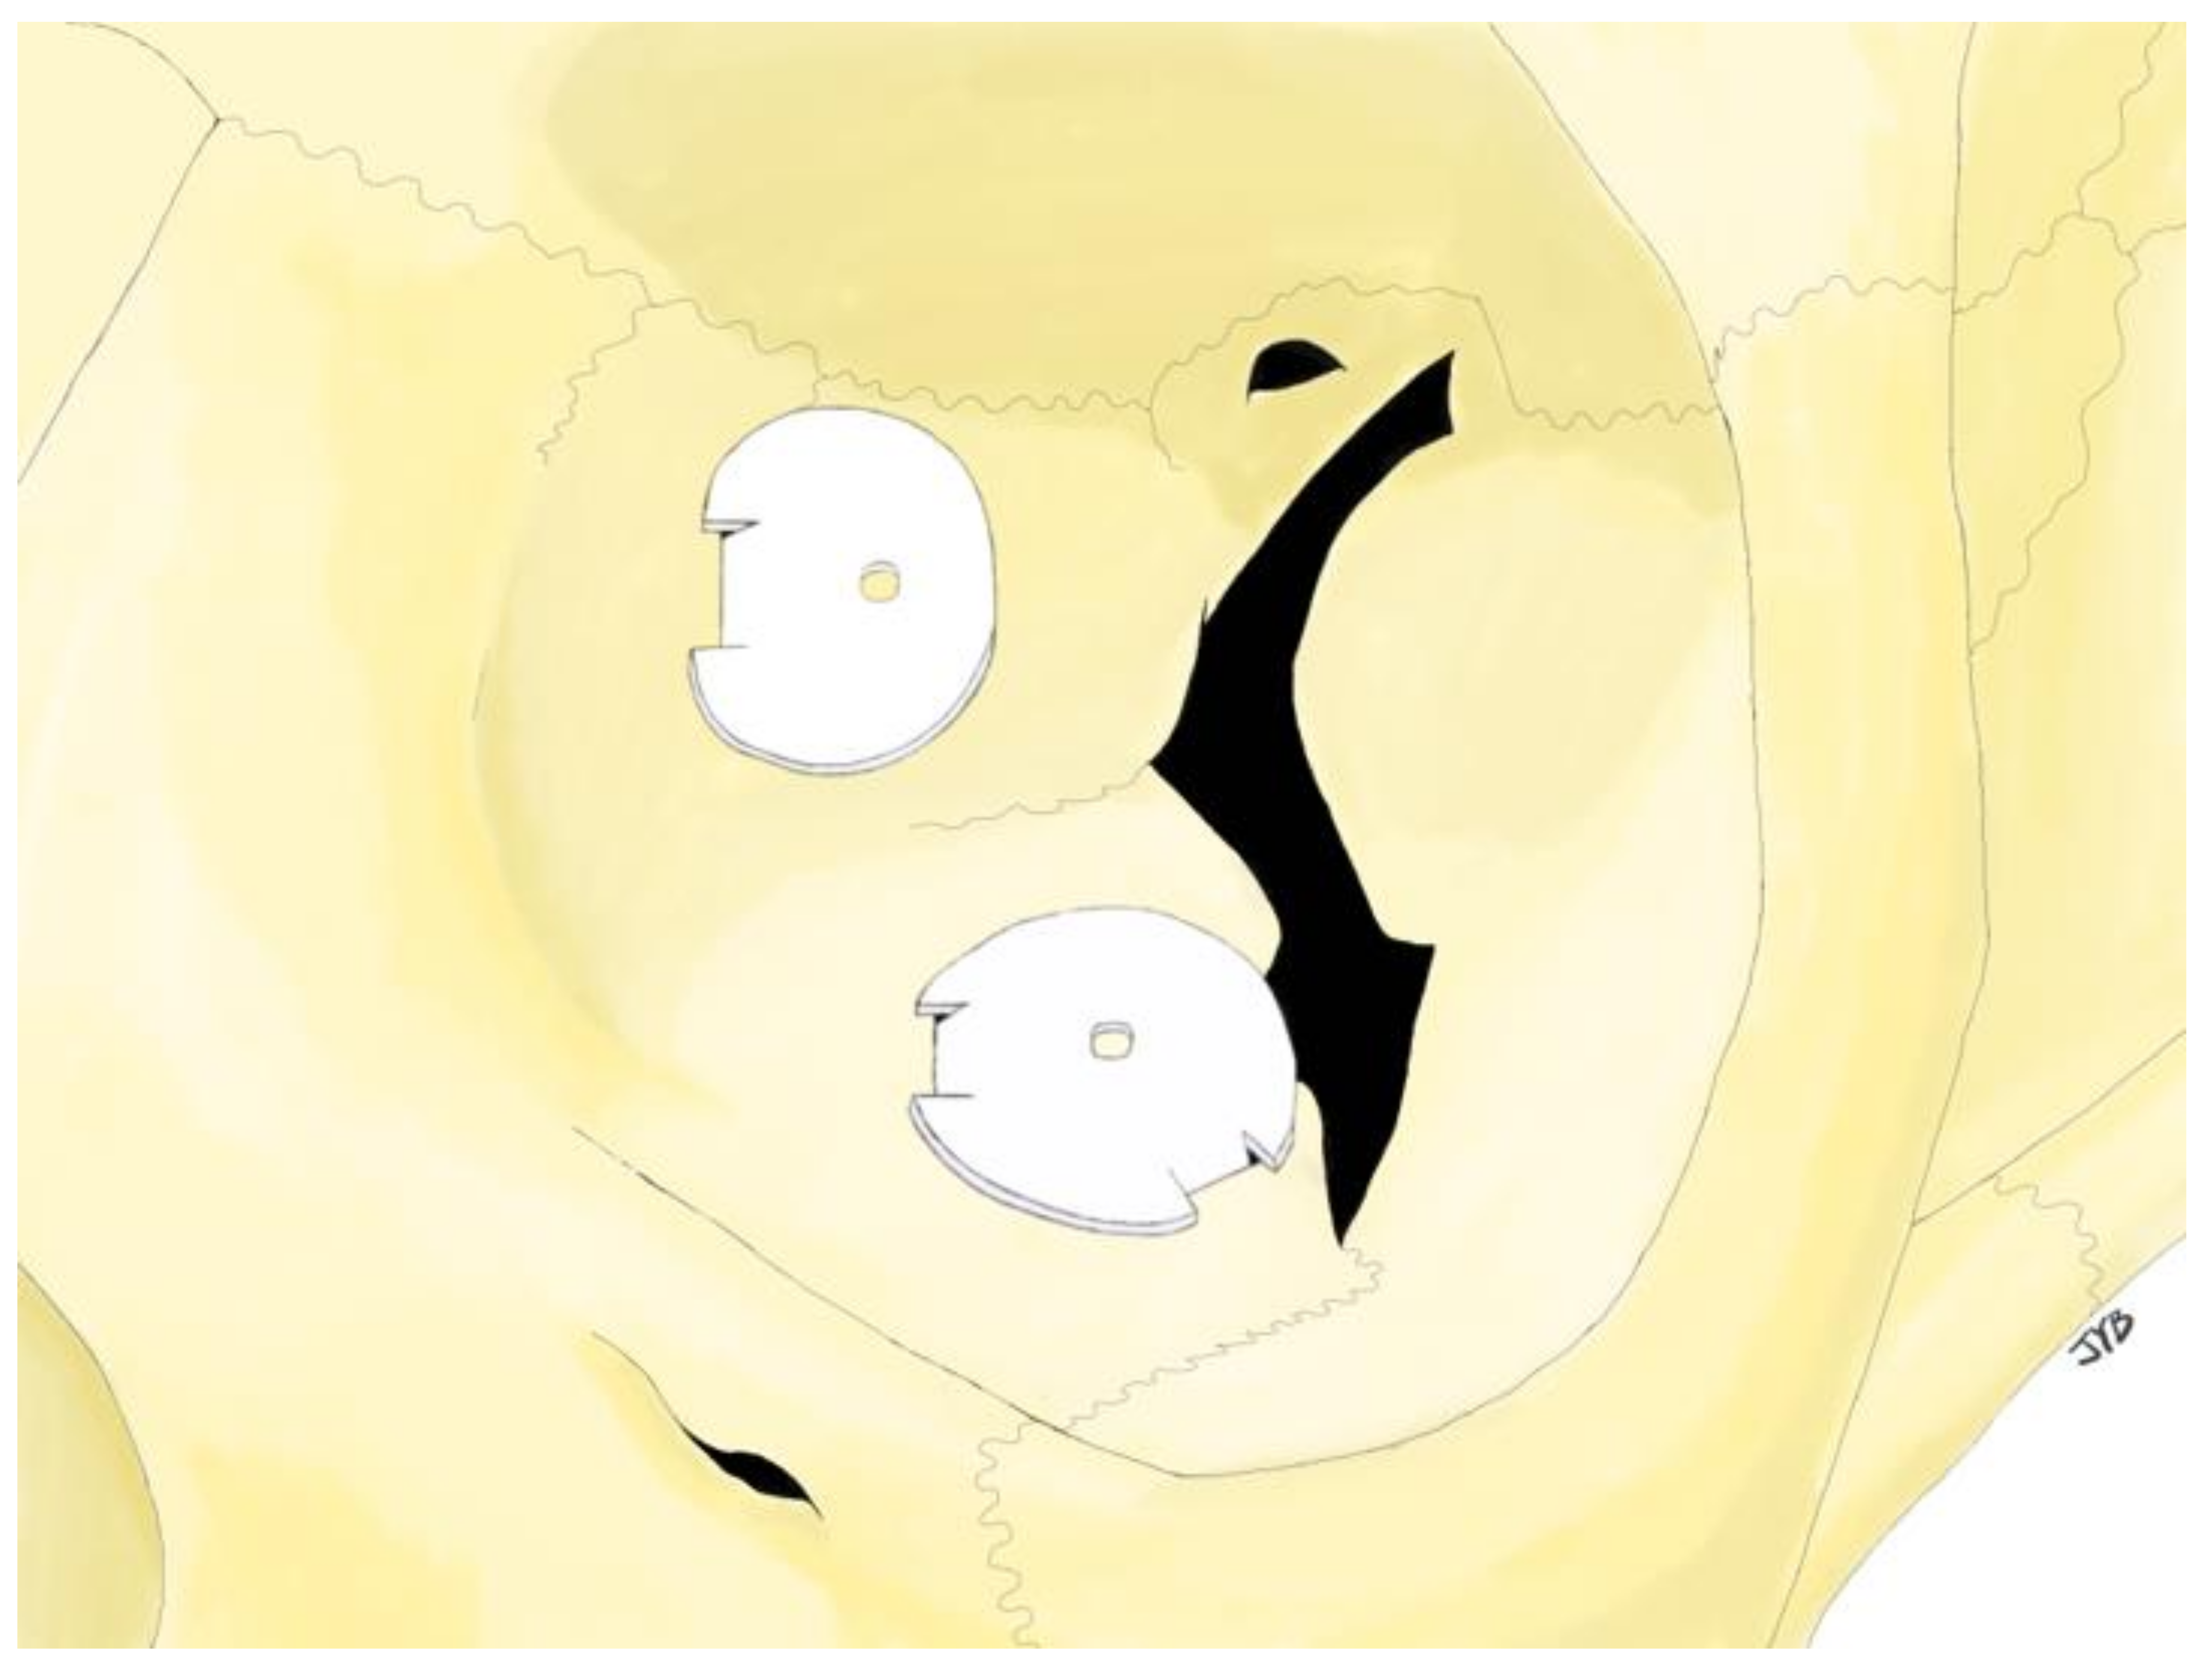

2.2. Surgical Procedure